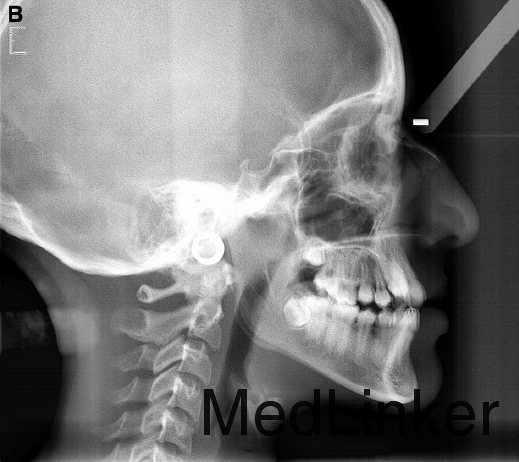

诊断:上牙弓严重横向不调。治疗:上颌颊侧骨皮质切开术+固定矫治+上颌腭侧固定扩弓。上颌上拖槽一周后行骨皮质切开术,如图,切开后全层翻瓣暴露骨皮质,于骨皮质上打孔,范围从牙槽骨顶端下方2mm到根尖下方2mm。根据牙槽厚度孔的深度从0.5mm到1.5mm不等,复位后间断缝合。同时腭侧粘接由带环,螺旋扩弓器制作的固定扩弓装置,即刻加力,转动完整的一圈。之后每周扩弓器打开1mm,连续8周,上颌牙弓被打开,扩弓器再维持2月,同时固定矫治器继续排齐整平。总疗程5个月2周。上颌宽度变化第一前磨牙间增加10mm,第二前磨牙间增加8.9mm,第一磨牙间增加8.3mm。但尖牙间宽度不变,这也是为什么扩弓后后期牙弓能够保持的原因,尖牙间宽度对维持牙弓稳定性非常重要。